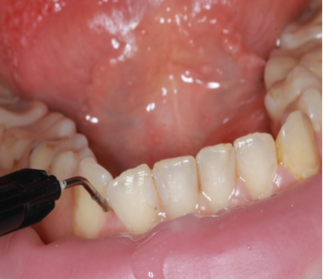

Пациентам основной группы 2 в первое посещения после обследования и профессиональной гигиены полости рта проводили антимикробную обработку пародонтальных карманов гелем «Метрогил-дента», осуществляя экспозицию препарата в течение 30 минут (Рисунок 7). Затем эту процедуру проводили ежедневно в течение 7 дней.

| Рисунок 7. После удаления зубных отложений пациентам основной группы 2 проводили обработку пародонтальных карманов гелем Метрогил-дента. |